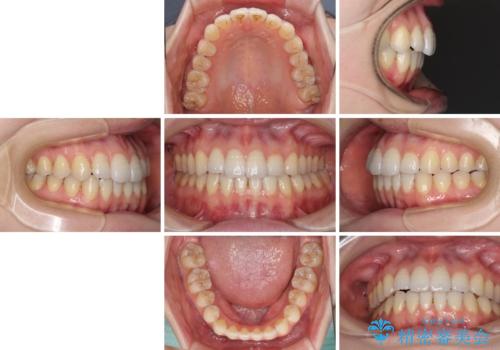

オープンバイトのインビザラインを用いた再矯正

- 矯正治療の後戻りを気にして来院された患者様です。

オープンバイト(前歯の開咬)と下顎骨の偏位による不正咬合が認められました。

骨格の偏位による不正咬合は改善しきれないことを理解いただいた上で、インビザラインにて矯正治療を行うこととしました。

オープンバイトは後戻りを起こしやすいため、極力そのリスクを軽減するため、奥歯を圧下させるように治療を進めていきました。

下顎骨の偏位が顕著であったため、上下の正中を合わせることはできませんでしたが、患者様には大変満足していただきました。